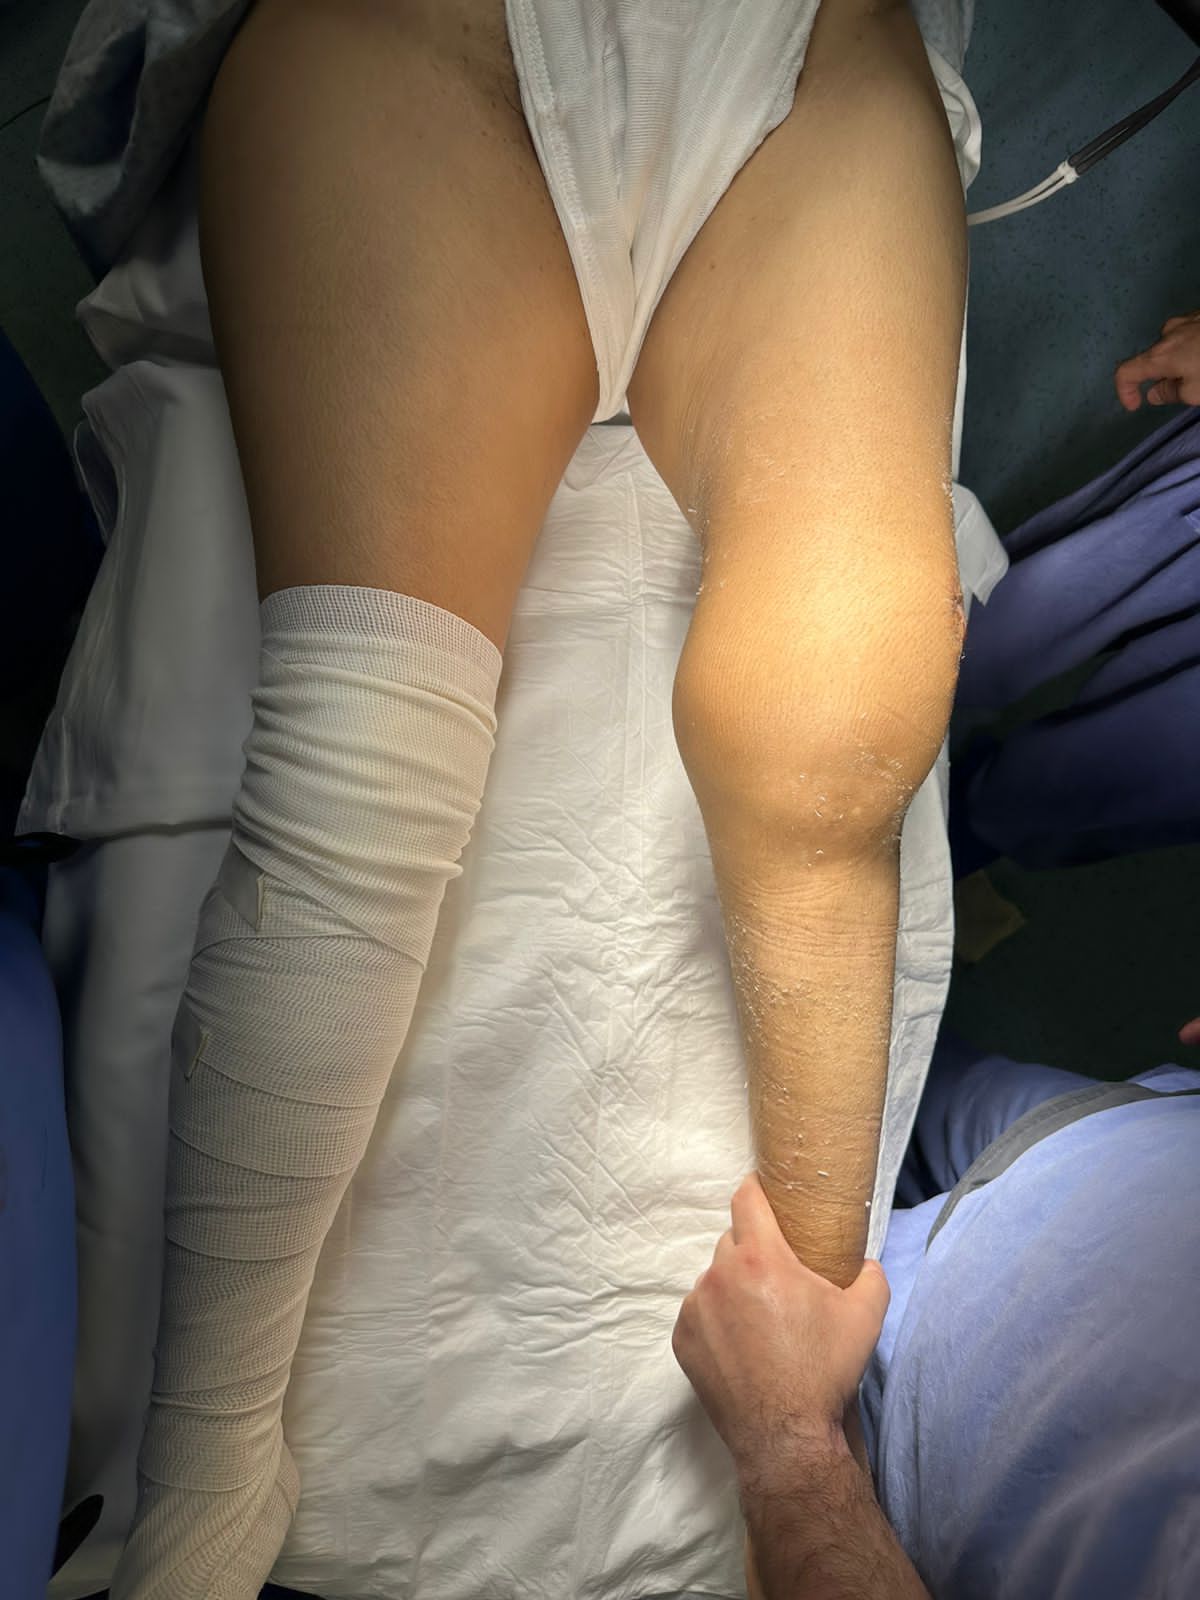

Hola, soy médico egresado de la BUAP y he tenido el honor de especializarme en Traumatología y Ortopedia en el complejo médico Magdalena de las Salinas, IMSS, con la validación de la UNAM. Además, tengo un Máster en Ciencias Médicas, centrado en el área quirúrgica de tumores músculo-esqueléticos, también en la Unidad Médica de Alta Especialidad, Magdalena de las Salinas.

• Tumores oseos

Tumores Músculo Esqueléticos

• Tumores Músculo Esqueléticos Cirugía de rodilla  •